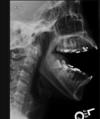

Fratura do processo odontoide

Tipo III de Anderson e D’alonzo.

Envolve o corpo de C2.

Estável, melhor prognóstico;